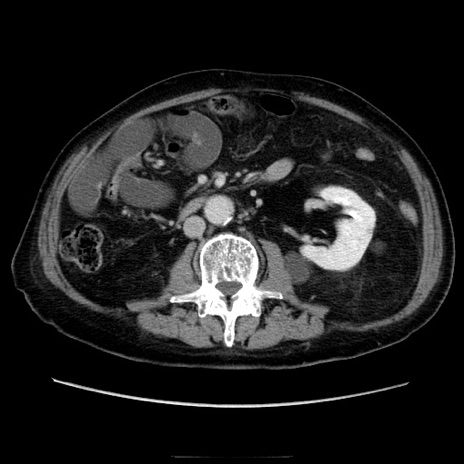

症例21(横断像)

【症例】70歳代男性

【主訴】腹痛

【現病歴】肝硬変・肝細胞癌にてかかりつけの方。約9時間前に食後より腹痛出現。症状が徐々に増悪し、嘔吐出現したため来院。

【既往歴】肝硬変、肝細胞癌(RFA、TACE後)

【身体所見】意識清明、表情苦悶様、BT 36℃、BP 129/78mmHg、P 88bpm、SpO2 97%(RA)、右上腹部から心窩部にかけて圧痛あり、反跳痛なし、筋性防御あり。

【データ】WBC 5800、CRP 0.16